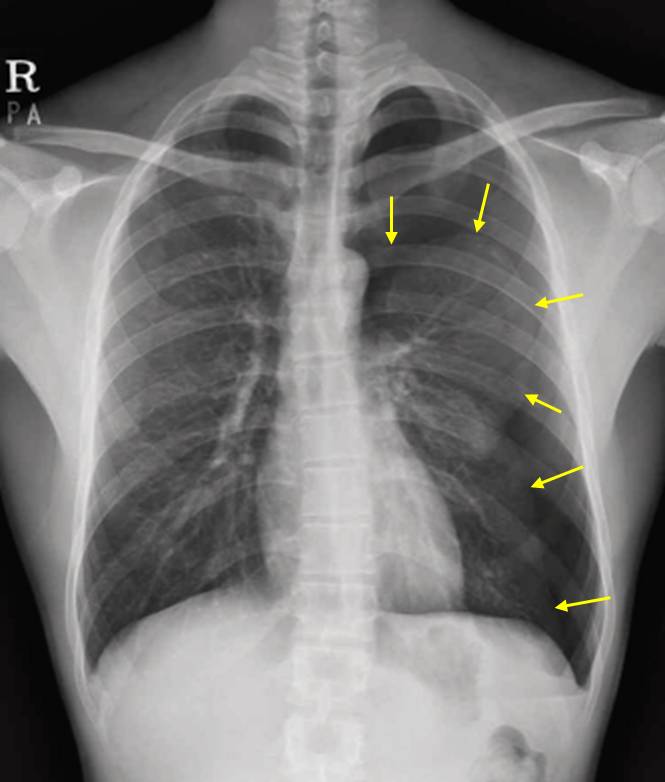

Img | CXR: Lt. pneumothorax |

CXR상 pleural line 및 distal vascular marking의 소실이 저명하므로 pneumothorax로 진단한다.

• CXR상 Lt. lung의 pleural line이 확인되며, 그 바깥쪽으로 pulmonary vascular marking의 소실이 확인된다. 2일 전 외상력을 고려할 때 traumatic pneumothorax로 진단할 수 있다.